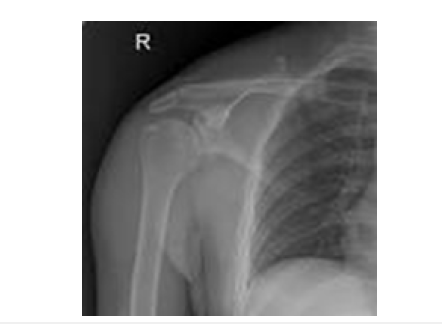

Shoulder Dislocation (SD) is a significant problem as pathological damage that occurs is high and contributes up to 60% of all major joint dislocations [2-4] and a costly and long drawn treatment in India. The incidence of shoulder dislocation is around 23 per 100.000 person per year [5]. Acute shoulder dislocation in youth and people below 40 years is usually caused by an accident or in traumatic sports events as was in our second and fourth cases [3,4]. Dislocations occur most frequently (96%) occasionally posteriorly, and rarely inferiorly [6]. The anteroinferior shoulder dislocation consists of four types, denoted by the humeral head position: sub-coracoid (70%), sub-glenoid (25%), sub-clavicular (4%) and intrathoracic (1%). The sub-glenoid subtype is a type of shoulder dislocation located beneath the inferior rim of the glenoid which is associated with potential axillary artery injury, brachial nerve plexus complications and Rotator Cuff Tears (RCT) (Figure 1) [7]. Anteroinferior dislocation occurs with the combination of abduction, external rotation, and extension [3,5]. Rapid hyperabduction of the arm at the shoulder, with extension at the elbow and pronated arm, usually results in sub-glenoid dislocation [3,4,6]. In India among SD cases Rotator cuff injuries are around half of cases, fractures in one third and neurological damage in 5% of cases. Anterior shoulder dislocation & concurrent rotator cuff tears are common in older individuals, possibly due to the weakening of posterior structures and among younger patient’s rotator cuff tears are rare due to stronger posterior shoulder structures [8].

Figure 1:

Investigations: Radiographs (X-ray) confirmed anterior dislocation and no fractures (Hill-Sachs, Bankart lesions, greater tuberosity fractures). He underwent surgical intervention, physiotherapy and recovered complete range of movements in about 16 weeks.